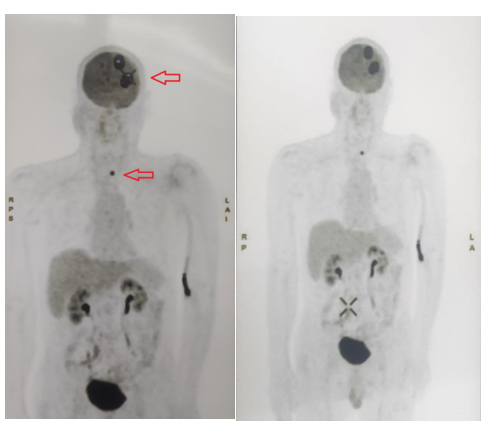

– Bệnh nhân được tiến hành chụp PET/CT toàn thân:

+ Hình ảnh 2 khối tổn thương ở nhu mô não thùy đỉnh – chẩm trái, kích thước lần lượt là 19x38mm và 23x48mm, tăng hấp thu FDG (SUVmax: 22,4); phù não rộng xung quanh, đè đẩy đường giữa sang phải 8mm.

+ Hình ảnh nhân giảm tỷ trọng ở thùy trái tuyến giáp kích thước 9x11mm, tăng hấp thu FDG (SUVmax: 12,6).

Hình ảnh 2 khối tổn thương ở nhu mô não thùy đỉnh – chẩm trái và hình ảnh nhân giảm tỷ trọng ở thùy trái tuyến giáp( mũi tên màu đỏ)